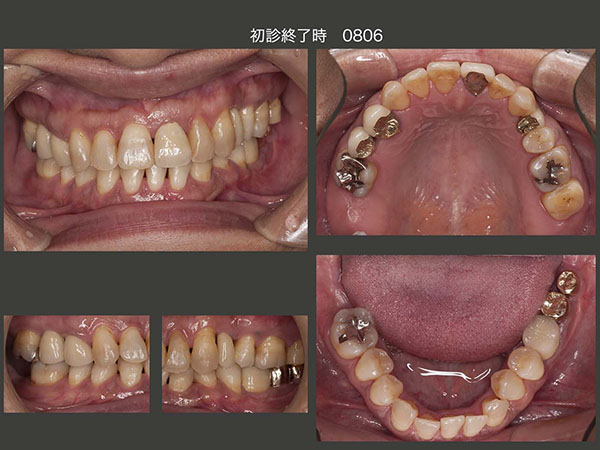

主訴の左上1を仮に修復し,一通りの基本治療を行った後の2006年2月,右上8の矮小歯を右上5部に移植した.さらに4月に,対合歯のない右上7を頰舌側に分割し,それぞれを左下に移植するという比較的難易度が高い移植を行った.続いて5月に,歯科矯正するに伴って必要がなくなる,舌側転位している左下2を左下の一番奥に移植した.これで左下は3本移植されたことになる.

左下の移植歯も固定源に利用し,06年11月に,下顎の歯科矯正に取りかかった.なお上顎は,少し前の8月から歯科矯正を開始している.08年3月,左上4部に,直径3mmの細いインプラントを植立した.ここは暫く人工歯を接着していたが,時々外れるので仕方なくインプラントを用いた経緯がある.両側がバージントゥースであり,しかも審美領域であることから今でも,補綴設計に悩む所である.